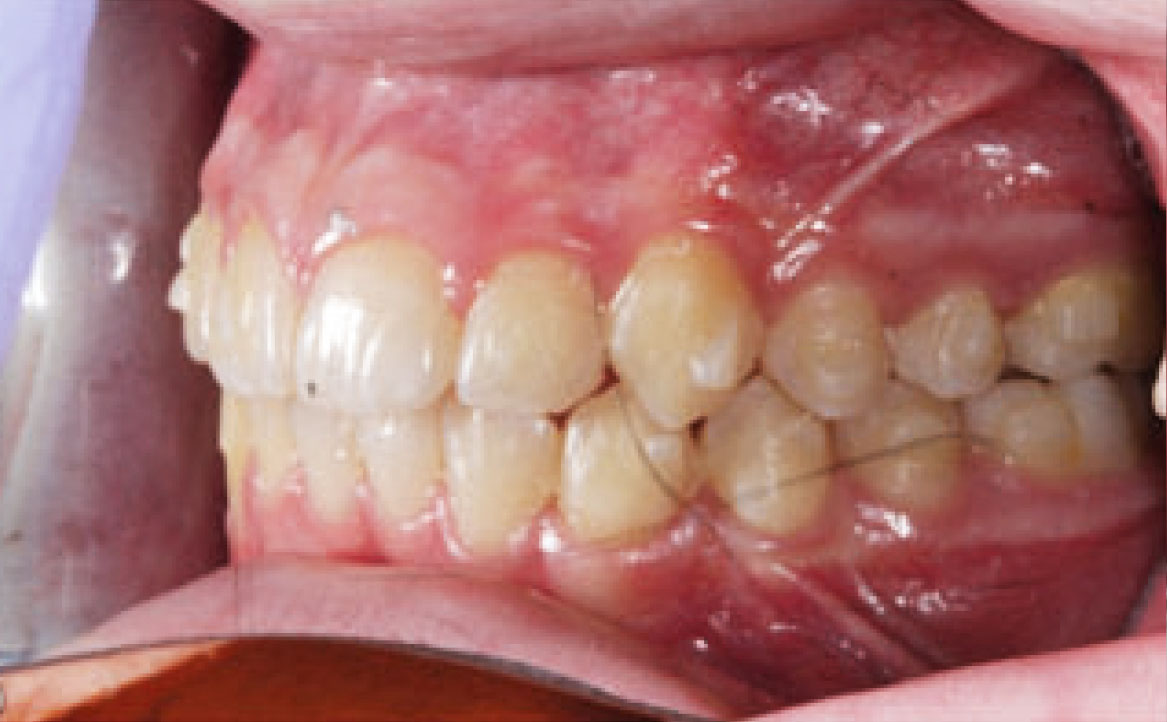

Dall’esame obiettivo intra orale si osservava una seconda classe canina destra e sinistra, una seconda classe molare destra e sinistra, e un diametro inter-canino e inter-molare ridotto sia in riferimento al mascellare superiore sia al mascellare inferiore (fig. 3A-3E).

A seguito del trattamento è stato osservato un miglioramento dell’igiene orale (fig. 5).